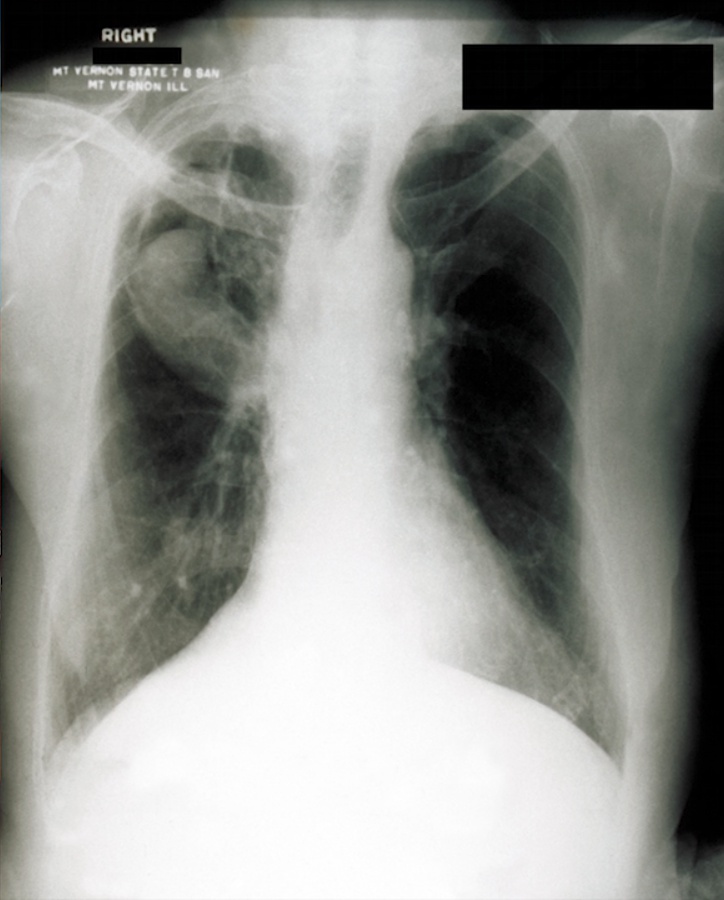

book with TB cacti: Histoplasma may mimic tuberculosis in presentation

Hilar calcifications: on Xray

coughing: pneumonia